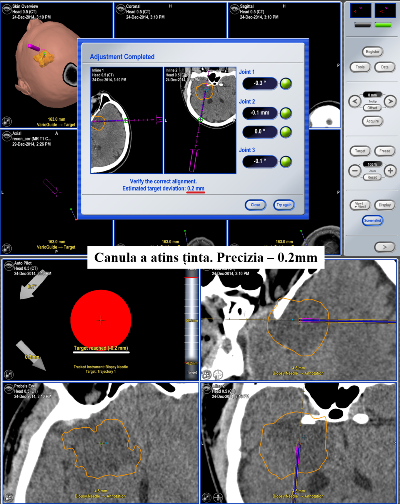

Toate aceste incomodități lipsesc în cadrul biopsiei cu utilizarea neuronavigației fără cadru stereotaxic. Astfel, procedura pentru pacient arată cât se poate de simplu. Pacientul intră în sala de operație fără cadru pe cap și iese de acolo cu procedura de biopsie realizată, localizarea și precizia biopsiei fiind confirmate pe masa de operație.

Pacientul S., a beneficiat de tehnologiile existente în volum deplin. Operația a durat 2 ore. Pacientul și-a revenit după o oră de la intervenția chirurgicală, iar peste o zi a fost externat. Pentru prelevarea biopsiei a fost aleasă o porțiune de tumoare localizată la adâncimea de 13 cm de la suprafață. Locul ales a fost țintit cu precizia de 0,2mm! Acest grad de precizie este suficient pentru toate biopsiile cerebrale, iar în anumite circumstanțe, sistemul poate fi utilizat și pentru tratamentul parkinsonismului.